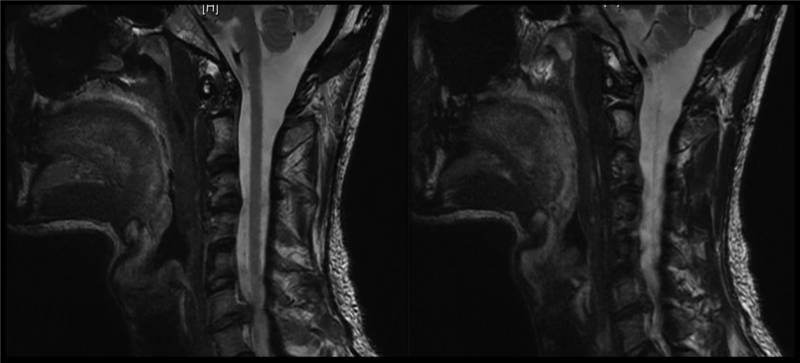

Bệnh nhân nam, 60 tuổi đi khám vì đau cổ tiến triển từ vài tháng nay, tê rần cánh tay phải, và bàn tay phải trở nên vụng về. Ông cho biết ngày càng mất thăng bằng trong đi lại, mặc dù vẫn còn khả năng làm công việc của một người quản gia. Dấu hiệu sinh tồn không có gì đặc biệt. Các xét nghiệm máu thường quy bình thường. MRI chụp có kết quả như hình 3.

- B. BN bị bệnh lý tủy cổ do thoái hóa cột sống cổ. MRI cho thấy khối thoát vị lớn, bên phải ở đĩa đệm C3-C4 gây hẹp ống sống dữ dội, tình trạng này làm nặng thêm tình trạng hẹp ống sống cổ bẩm sinh của BN (<13mm). Ở các tầng khác của cột sống cổ, các đĩa đệm lồi ít hơn và có tình trạng phì đại dây chằng, gây ra hẹp ống sống vừa phải. MRI có tiêm Gadolinium không có hình ảnh bắt thuốc cản quang của những thương tổn trong bệnh lý di căn, nhiễm trùng hoặc rối loạn thoái hóa myelin.

Hình 10. MRI cột sống cổ cho thấ hình ảnh thoát vị đĩa đệm cổ C6-C7.